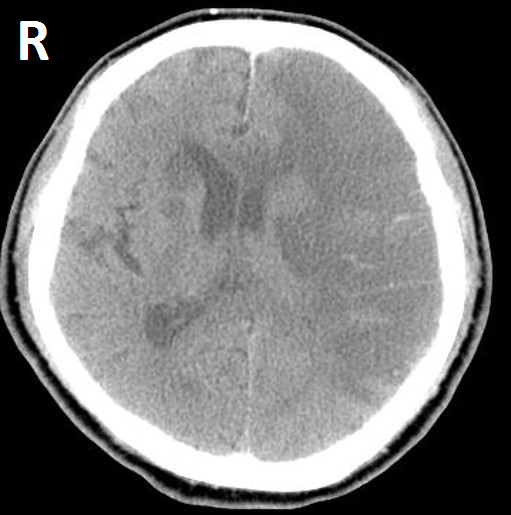

【111-1 醫學(四) 第46題】一位66歲女性病人,有高血壓及心律不整病史多年,被家人發現突然無法言語及右側肢體無力,之後意識逐漸昏迷,其腦部電腦斷層掃描如下,最有可能發生問題的血管為何?

詳解

破題關鍵

這是一位有高血壓和心律不整病史的病人,突然出現失語症和右側肢體無力,這是典型的急性腦中風表現。影像上,腦部電腦斷層掃描顯示左側大腦半球有大範圍的低密度病灶,這代表缺血性腦梗塞。結合臨床症狀和影像位置,指向左側中大腦動脈的灌流區域。